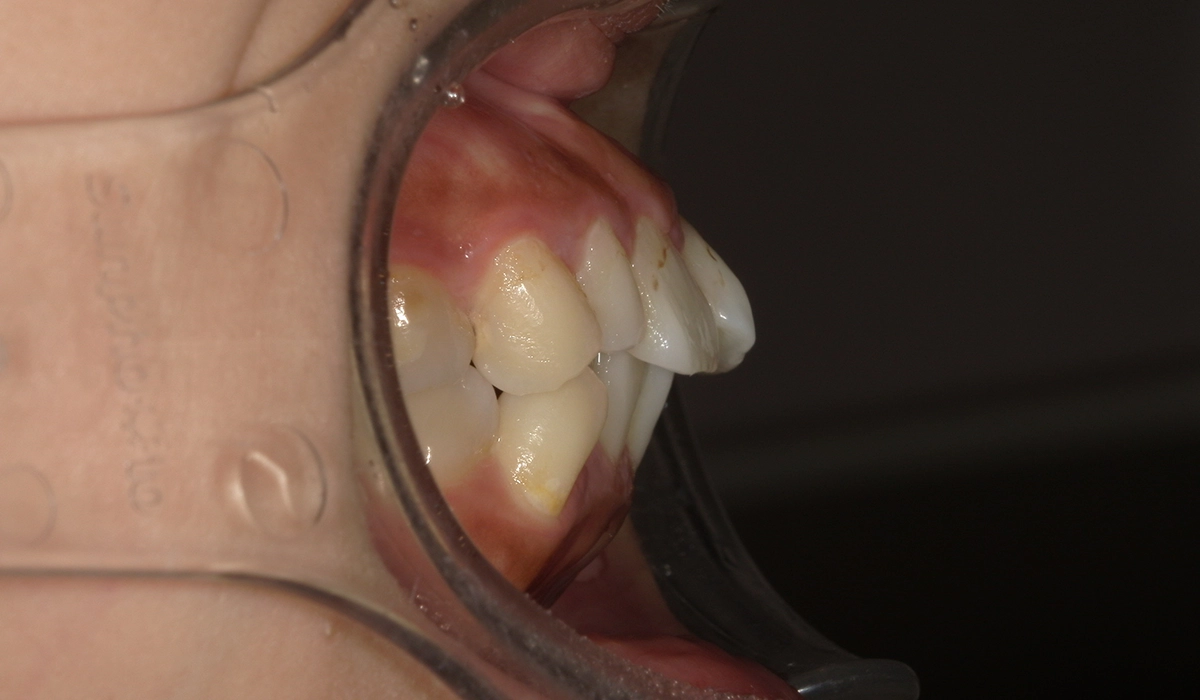

術前:右側

術後:右側